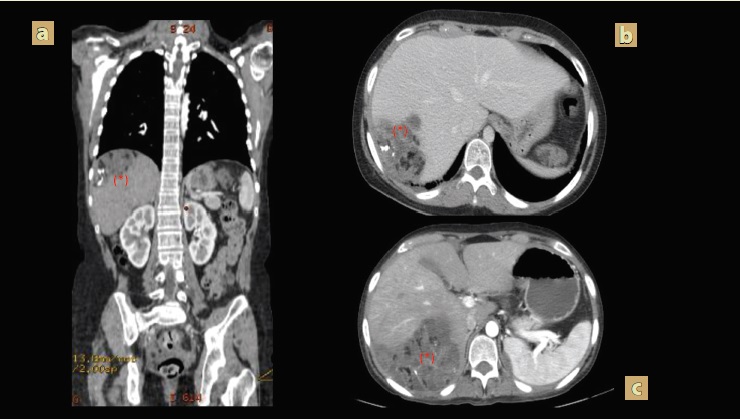

A los 3 meses del postquirúrgico inició con incremento del perímetro abdominal, se realizó tomografía abdominal contrastada de control, evidenciándose persistencia de la enfermedad a nivel retroperitoneal, así como tumor que abarcaba toda la pelvis, derrame pleural bilateral y ascitis (figura 1); reporte de resultados de laboratorio con hormona gonadotropina coriónica humana fracción beta negativa y alfafetoproteína negativa (tabla 1), por lo cual se indicó comenzar manejo con 3 ciclos de quimioterapia y posteriormente se le realizó una laparotomía exploratoria en la que realizaron la resección de tumoraciones intraabodminales con reporte de patología con teratoma maduro en las 3 muestras tomadas. En seguimiento con oncología y tomografía abdominal de control, hubo evidencia de aparición de tumoración hepática (figura 2) sugerente de actividad metastásica, por lo que requirió un nuevo procedimiento quirúrgico y se realizó la intervención con evidencia de tumoración que ocupa la cara posterior y superior del hígado en segmentos VI y VII, así como dos tumoraciones a nivel del retroperitoneo; se realizó la resección de estas, todas con reporte histopatológico de teratoma quístico maduro sin evidencia de neuroepitelio.

Figura 2 Tomografía abdominal con recidiva tumoral hepática en corte axial a) simple y b) contrastada c) reformateo coronal contrastada, hígado con parénquima heterogéneo a expensas de una imagen con bordes lobulados, localizada segmentos VII-VIII contenido heterogéneo por presencia de imágenes iso, hipo e hiperdensas en su interior en relación a componente graso, calcio y líquido (*).